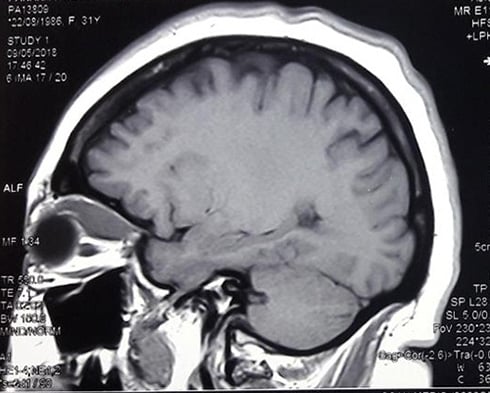

Existen múltiples neuropatías ópticas. La característica principal es la disminución de la visión de uno o ambos ojos, usualmente asociadas a la disminución de la visión de colores y el campo visual. Puede tener varios orígenes: lesiones inflamatorias, compresivas, tóxicas, nutricionales, circulatorias, traumáticas, congénitas y relacionadas a neoplasias.

Es la inflamación aguda o subaguda del nervio óptico de uno o ambos ojos. Se caracteriza por disminución de la visión, precedida usualmente por dolor ocular o retro ocular. Puede ser un cuadro aislado o también relacionado a enfermedades virales, inmunológicas o del sistema nervioso central.

Existen diversos tipos. De inicio repentino o lento, y también intermitentes y progresivas. El origen puede estar en el nervio óptico, en el sistema nervioso central o en sistema cardiovascular inclusive.